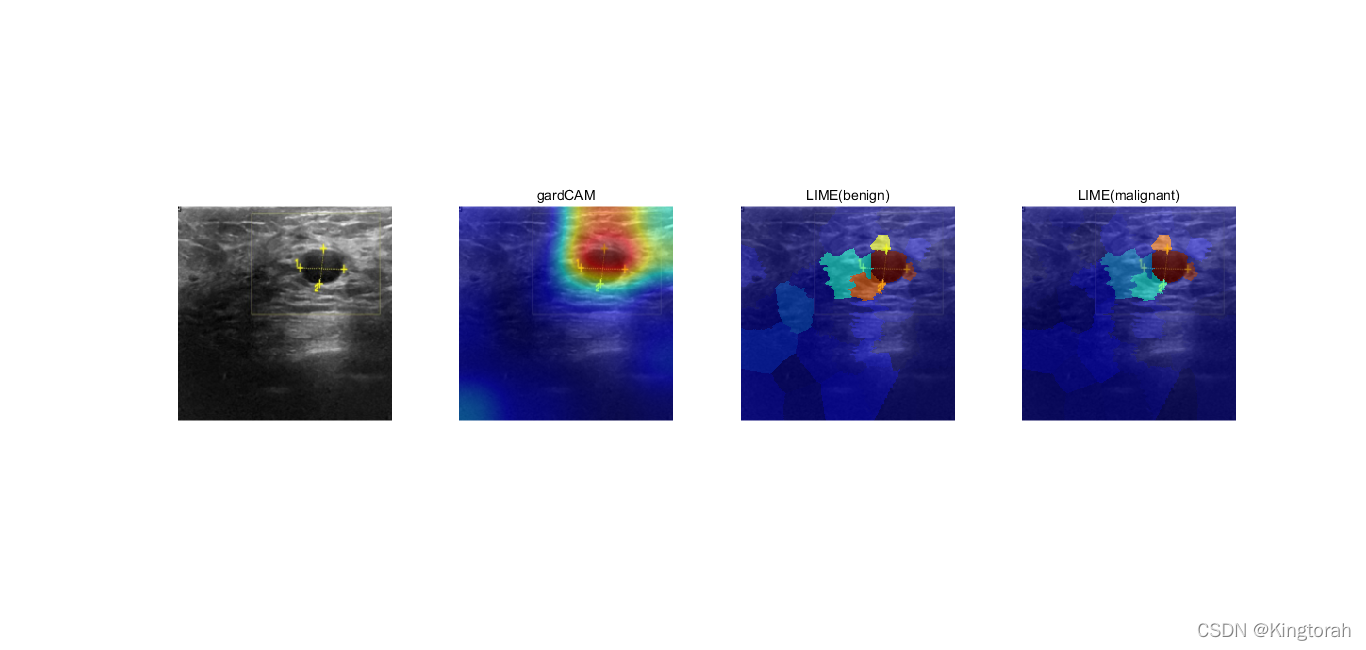

然后就可以配置可解释方法的几个函数(以gradCAM和LIME为例)其中LIME做了良性和恶性的对比

,也就是比较在同一个影像图片中模型基于不同的分类的关注点。

我们可以看到输出结果如下:

从图片中可以看出,对于gardCAM和LIME红色的区域都是模型训练过程中感兴趣区域,基本都处在结节处,其余颜色包裹在边界周围,而传统的医生阅片也是观察结节的边界形状规则度、清晰度和内核回声度,实现了模型的可解释性.